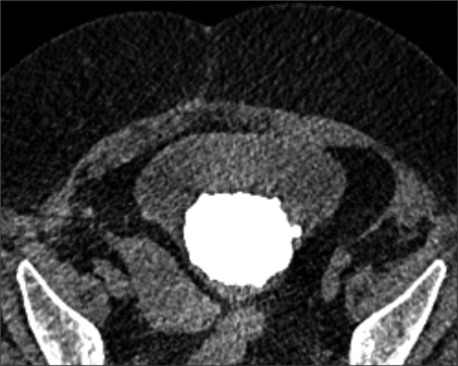

Results: Seven patients underwent a total of nine PCCLs between 2019 and 2023. Sone burden ranged from 4 to 10 cm. No intraoperative complications were faced. Three patients had residual stone fragments < 7 mm in size. Suprapubic catheter was removed between days 0 and 3 postoperative. Cystostomy was left to close spontaneously, none of the patients developed peritoneal leak after removal. Patients with Mitrofanoff channel reported no leak or compromise to the continued mechanism. Predominant stone composition was magnesium ammonium phosphate (struvite) in seven cases.

Abstract Image